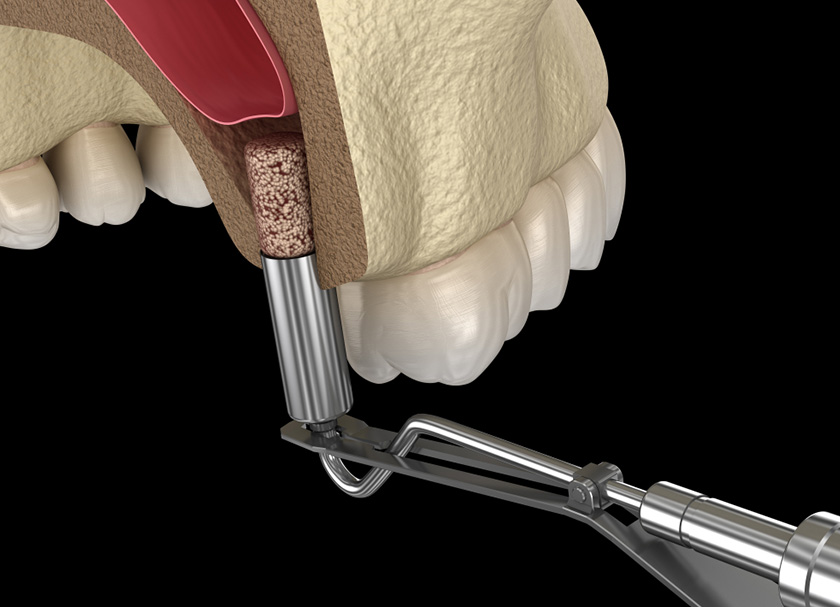

- A customised, prefabricated guide is placed on the upper jaw. This allows the surgeon to access the sinus through a key hole tissue punch

- The bone is drilled through the keyhole to make space for the implant to be placed.

- A bone graft is placed through the keyhole to support the freshly elevated membrane

- An implant is placed within the fresh osteotomy and covered with a healing screw.